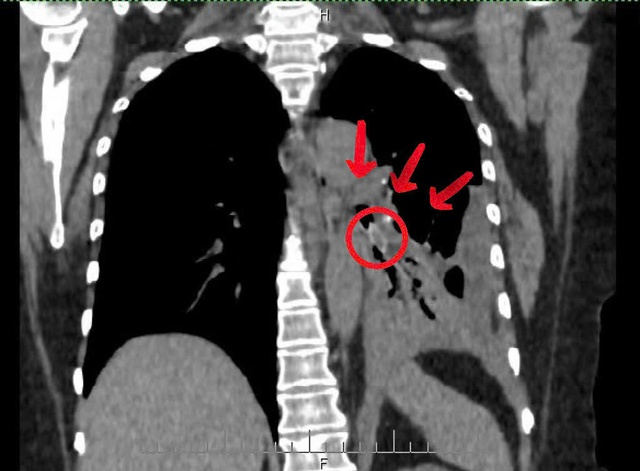

Ca thứ nhất là ông V.T.Đ. (65 tuổi, phường Quỳnh Mai, Nghệ An) nhập viện ngày 22/11 trong tình trạng khó thở, đau ngực trái. Kết quả chụp cắt lớp cho thấy có dị vật sâu trong đường thở. Ê - kíp cấp cứu phối hợp bác sĩ nội soi tiến hành can thiệp khẩn.

Qua nội soi phế quản, bác sĩ phát hiện một hạt hồng xiêm trơn bóng mắc tại phế quản phân thùy 4 - 5 trái, gây viêm mạnh và nhiều mủ trắng che kín lòng phế quản. Sau gần 30 phút thao tác tỉ mỉ, dị vật dài khoảng 2 cm đã được gắp ra an toàn.

Ca thứ hai xảy ra với chị L.T.H. (29 tuổi, xã Minh Châu, Nghệ An), nhập viện ngày 17/11 vì ho kéo dài, đờm đục và đau ngực tăng dần. Tình trạng kéo dài từ tháng 8 sau một bữa ăn nhưng do có tiền sử hen, triệu chứng dễ bị nhầm sang cơn kịch phát, khiến chị đi khám, điều trị nhiều nơi nhưng không cải thiện.

Hình ảnh trước và sau gắp dị vật là mảnh xương dài hơn 1 cm trong phế quản bệnh nhân L.T.H.

Qua nội soi phế quản, các bác sĩ phát hiện một mảnh xương dài hơn 1 cm bít gần hoàn toàn phế quản thùy dưới phổi phải. Dị vật được lấy ra thành công, người bệnh hồi phục nhanh sau đó.